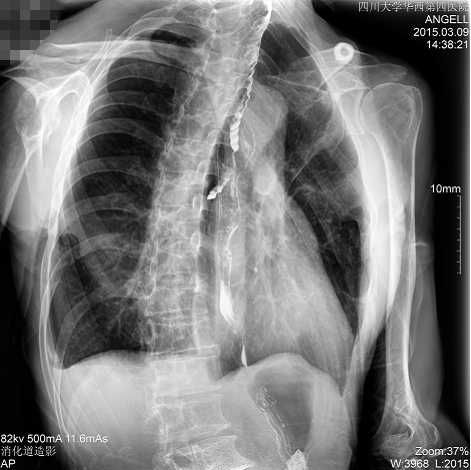

如下圖所示:該患者因吞咽時感到很難受,進食時也經常咳嗽故就醫診斷。使用多功能dr為病人進行消化道造影診斷,要求他吞鋇后發現,食道各段通過順利,形態規則,雙側梨狀窩不對稱左側稍淺,多次吞咽動作后,仍見鋇劑滯留,并見鋇劑進入氣管,屬于會厭征陽性。會厭功能紊亂,鋇劑進入了氣管。

圖為斜位:通過動態影像可以清楚看到鋇劑進入了支氣管道

通過多功能dr可以診斷該病人的癥狀為會厭功能紊亂,鋇劑進入到了氣管。而在動態透視下可以清晰的觀察到鋇劑從何處進入氣管,可清晰顯示食管粘膜結構。使用多功能dr其獨特的視頻采集技術,可實時保存視頻并能實現900萬像素實時點片,才能獲取這樣清晰的病灶點。而常規dr只能拍攝靜態片,且成像效果大打折扣,因此較難確診病灶。